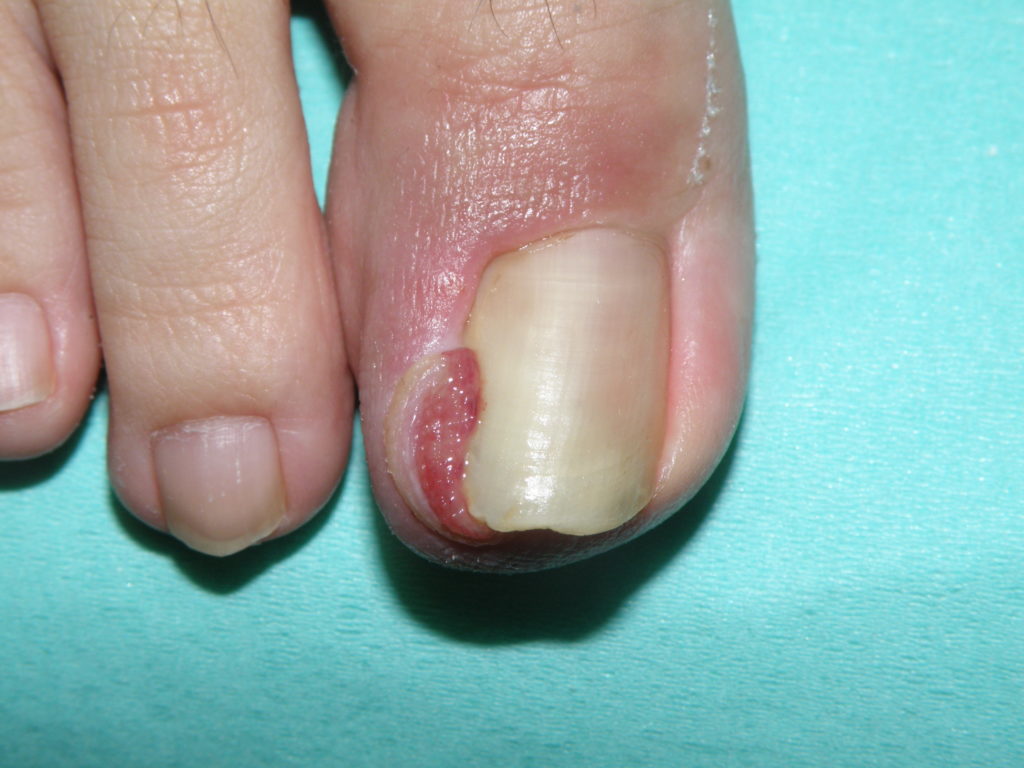

陥入爪は、爪の端や角が爪の隣の皮膚に食い込むことで発生します。陥入爪になりやすいのは足の親指です。

足の爪が爪床周囲の皮膚に再び成長する場合、それは陥入爪として知られています。これらは痛みを伴う場合があり、感染症を引き起こす可能性があります。

陥入爪は痛みを伴うことがあり、通常は段階的に悪化します。

初期段階の症状には次のようなものがあります。

• 爪の隣の皮膚が柔らかくなったり、腫れたり、硬くなったりする

• つま先に圧力がかかると痛い

• つま先の周りに体液が溜まる

足の指が感染すると、次のような症状が現れることがあります。

• 赤く腫れた皮膚

• 痛み

• 出血

• にじみ出る膿

• つま先の周りの皮膚の過剰成長